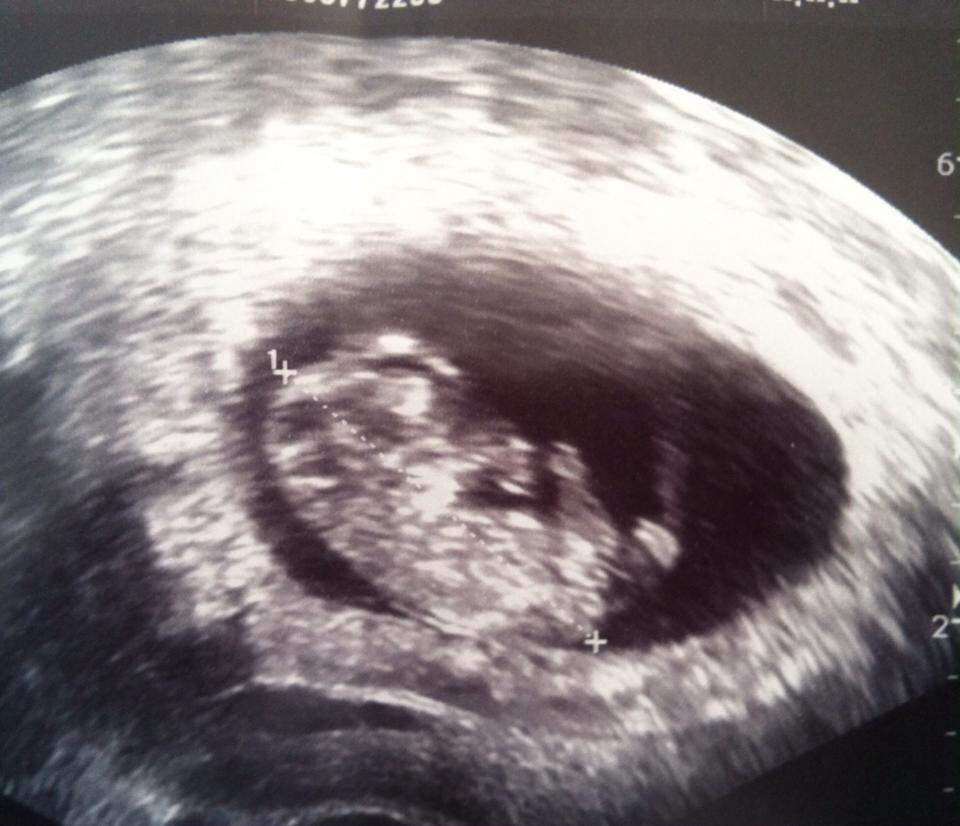

jeg har desværre ik noget scannings billed endnu. men overvejer og tage til scanning i morgen hvor jeg også ville være de der 10 uger..

men jeg er nys omkring hvor meget man kunne se og om den lille bevægede sig ?

Man kunne se arme, ben, krop og hoved og til tider navlestreng og selvfølgelig et lille hjerte blinke.

Den bevægede sig ikke rundt, men hun sagde at det kunne være at om 5 min så lå den slet ikke stille -men hun var glad for at den lå stille ellers kunne hun ikke måle :-)